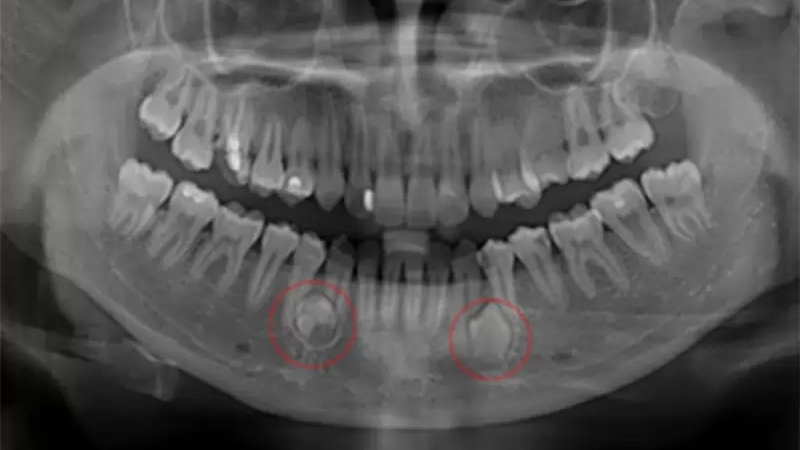

Cần chụp X-quang răng để chẩn đoán nang chân răng

Để chẩn đoán nang chân răng chuẩn xác hơn, bạn cần chụp X-quang răng. Trên phim, nang được hiển thị dưới dạng vùng sáng hình tròn hoặc oval dính liền với một chân răng đã chết tủy. Răng tương ứng với nang có lỗ sâu rộng, chóp chân răng nằm trong vùng thấu quang. Dây chằng quanh răng bị giãn rộng. Bên cạnh đó, bạn cũng có thể dễ dàng thấy các răng bên cạnh bị nghiêng hoặc di chuyển.

Nang chân răng lớn phát triển trên xương hàm trên có thể mở rộng về nhiều hướng khác nhau. Nếu nang nhiễm khuẩn, ranh giới nang sẽ không rõ ràng do sự giãn mạch xảy ra do viêm và tiêu xương xung quanh răng.